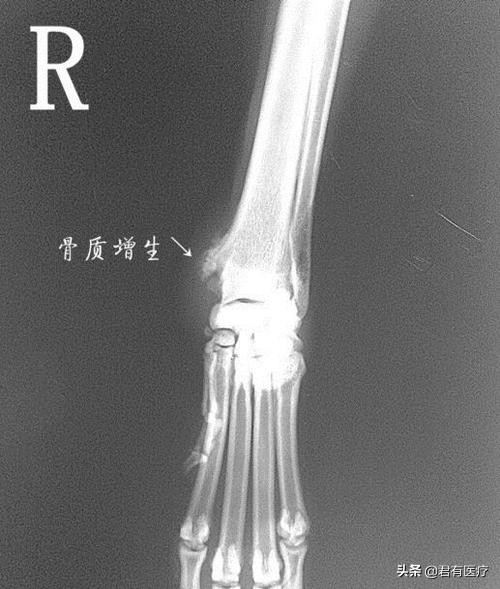

"骨刺"也叫骨质增生、骨赘,西医没有"骨刺"一说,规范叫法是"骨疣"。骨刺像脸会长皱纹、人体会衰老一样,是一种自然的老化现象,并不是疾病。

实际上,骨刺的形状并不像"刺",而是光滑的、鳞片状的,也不会"扎"到肉里,多数骨刺没有症状。

为避免骨与骨直接磨损,肌体代偿机制促使骨关节边缘增生,以保护关节。从这个角度上来讲,可以说,骨刺是骨骼的修理工。

通过骨质增生(骨刺)增加骨骼表面积,减少单位面积上的压力,使关节更加稳定。